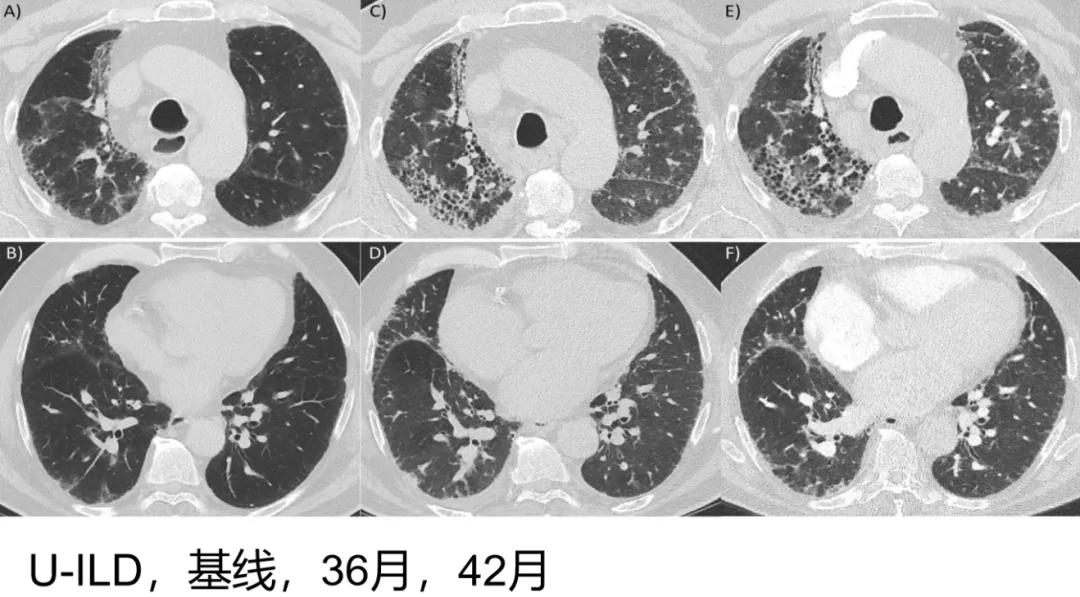

病例2 [23]

这个病例早期还是一个比较轻的、不能分类的间质性肺疾病。三年后更加严重,已经有蜂窝样改变伴牵拉支气管扩张,随着病程延长更加明显了,这也是一个具有进展表型的纤维化型间质性肺疾病。

(来源:Wong et al. Respiratory Research (2020) 21:32)